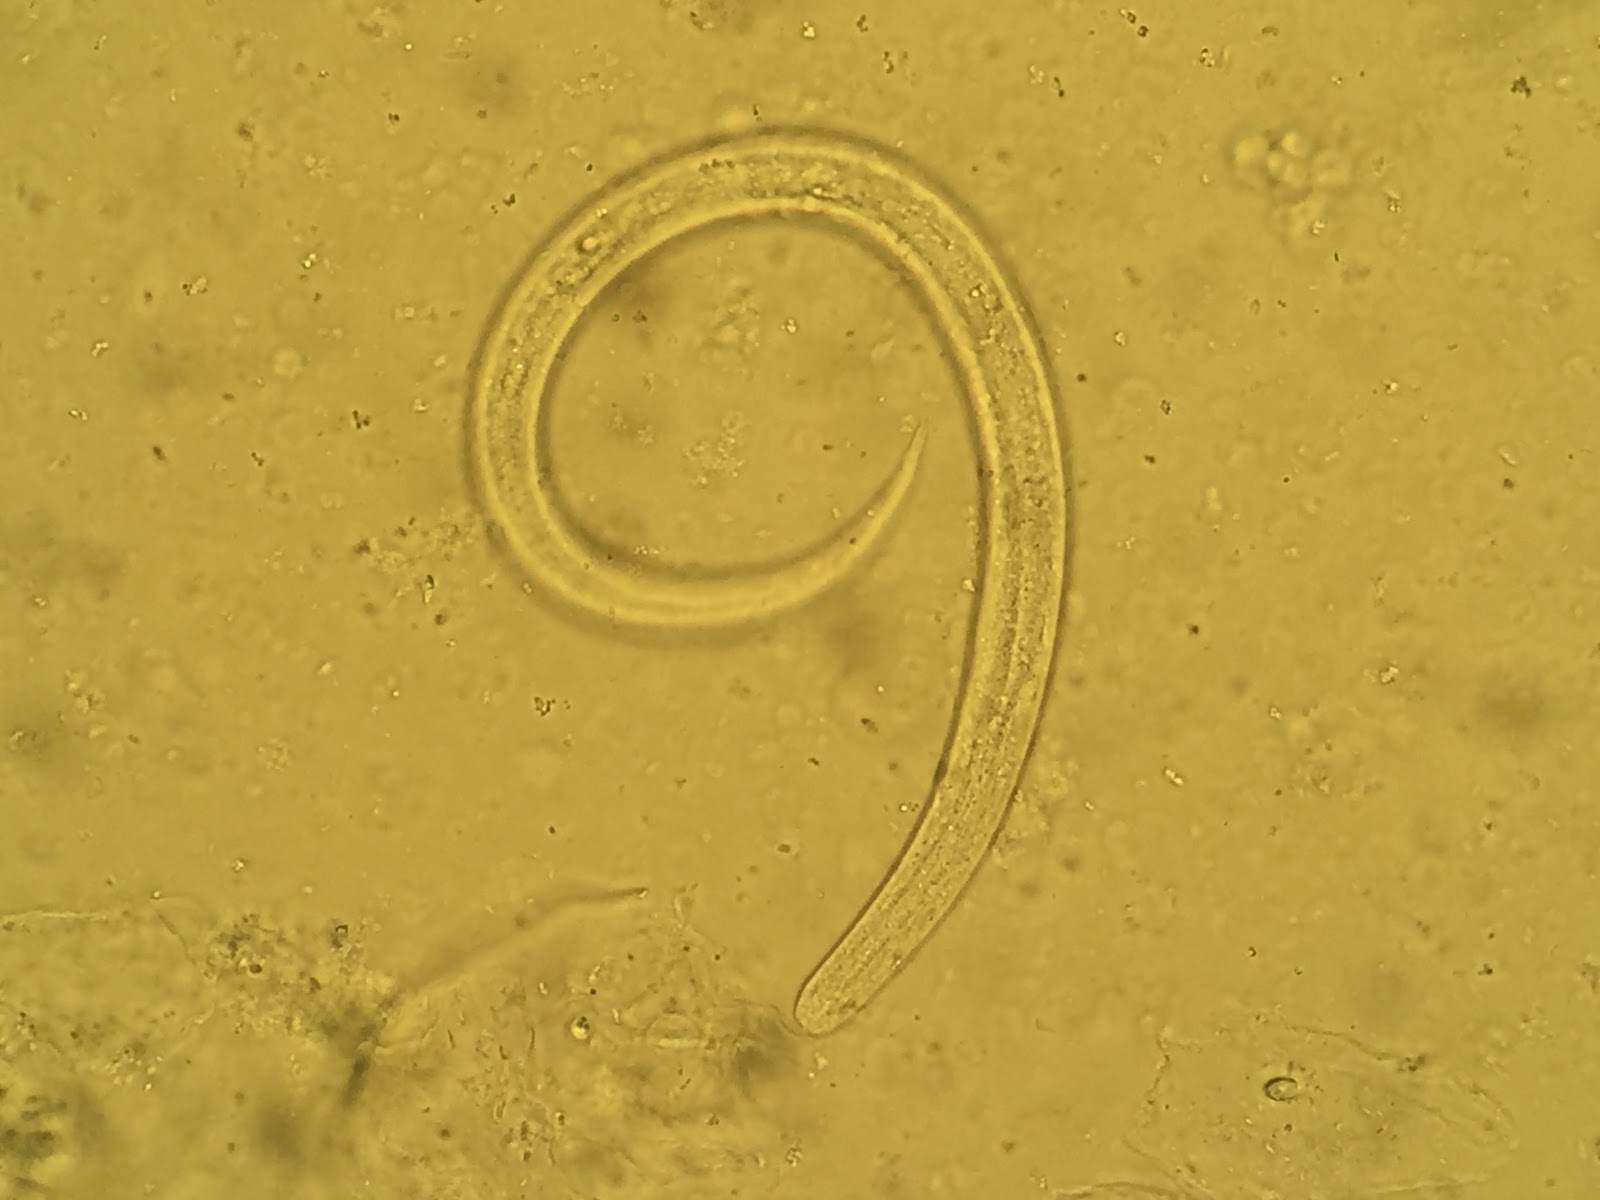

Answer to the Parasite Case of the Week 765: Strongyloides stercoralis L4 larvae

As noted by Idzi Potters, "The presence of a relatively large genital primordium confirms Strongyloides. The apparently tapered tail (not notched) together with the size of the larva point towards the fourth-stage autoinfective larva (L4)."

For those of you who were thinking these were autoinfective filariform (L3) larvae, you were very close! L4 larvae are the next stage in development after autoinfective L3 larvae and may be potentially detected in human respiratory specimens. Richard Bradbury and his colleagues just published a very interesting article in the Journal of Clinical Microbiology on the presence of L4 S. stercoralis larvae in two separate cases, and we received permission from JCM and the Editor-in-Chief to reproduce some of the images here.

The major differences between S. stercoralis L3 and L4 larvae are as follows:

- Length: autoinfective L3 are <600 µm and L4 are ~800 µm

- Genital rudiment: small in L3 and elongated in L4 larvae

- Vulva: may be visible in L4 (not L3)

- Tail: L3 is notched whereas L4 is more tapered